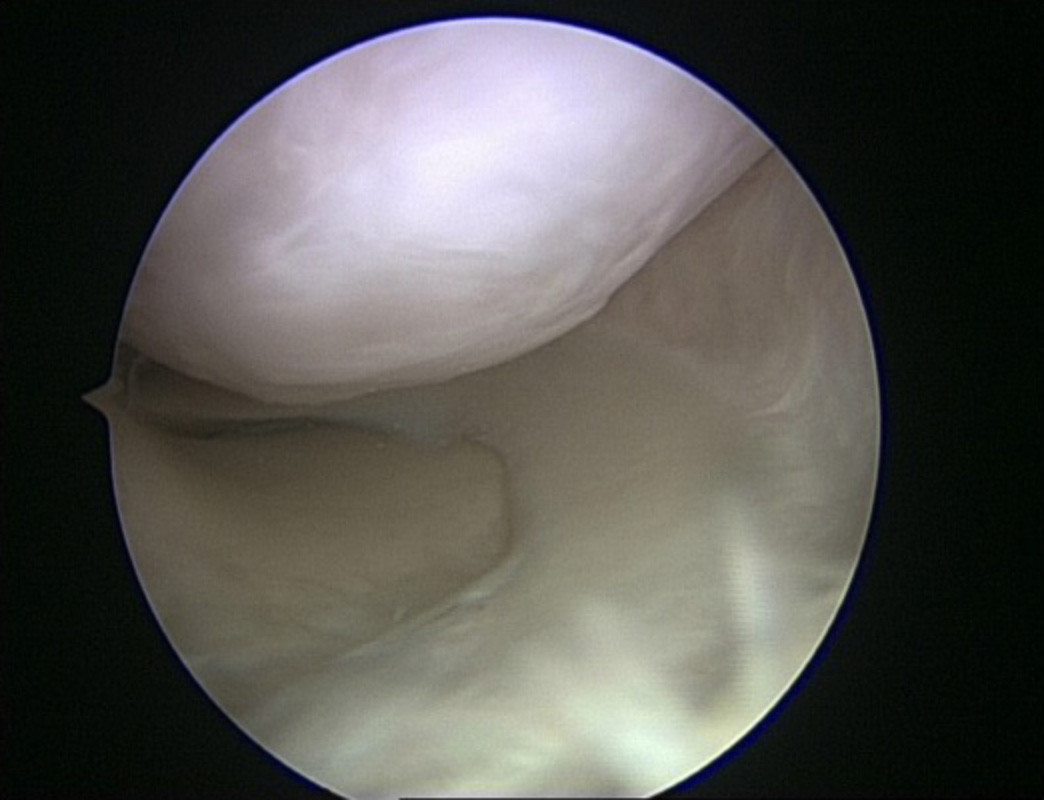

Ausbruch eines Knorpelstückes aus der Kniescheibe

Bei Unfällen können Bruchstücke aus der Gelenkfläche herausbrechen. In diesen Fällen besteht die Möglichkeit diese Bruchstücke wieder in den entstandenen Defekt einzupassen und mittels resorbierbarer Implantate zu refixieren. Langfristige Schäden für das Gelenk können somit so weit als möglich verhindert werden. Dies ist umso entscheidender als häufig Jugendliche und Kinder von diesen Verletzungen betroffen sind.